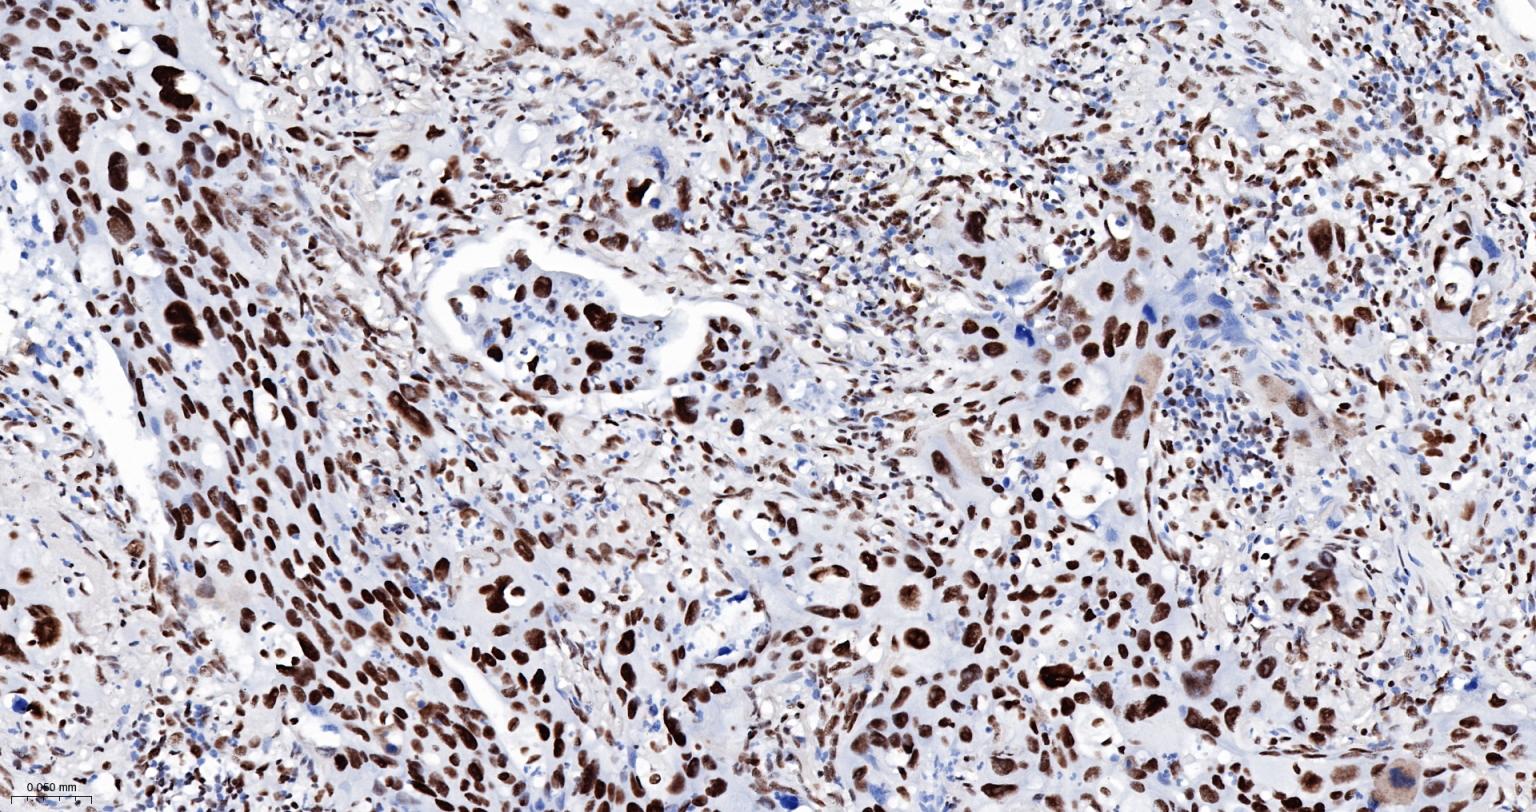

Paraformaldehyde-fixed, paraffin embedded Human Prostate Cancer; Antigen retrieval by boiling in sodium citrate buffer (pH6.0) for 15 min; The section was incubated with ARID1A Monoclonal Antibody, Unconjugated (bsm-61359R) at 1:200 overnight at 4°C, followed by conjugation to the bs-0295G-HRP and DAB (C-0010) staining.